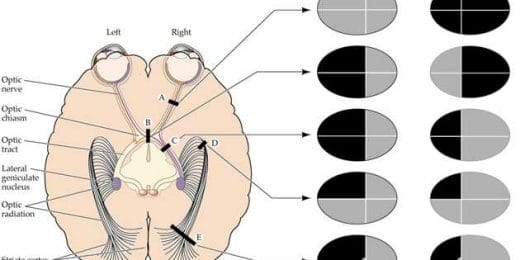

Visueel neglect

Neglect is een vrij zeldzame en onbekende aandoening. I...